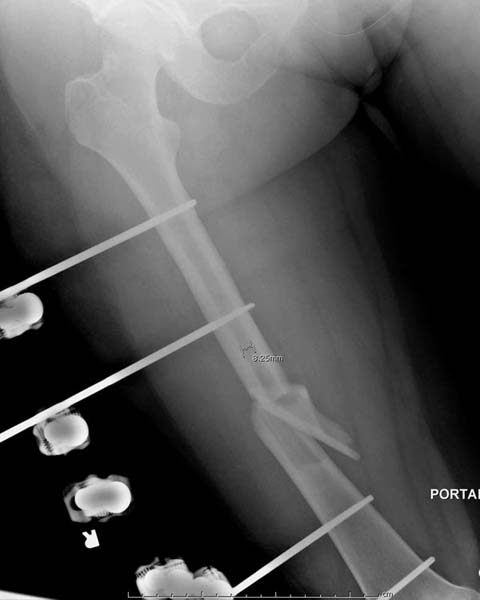

Около 11.00 вечера больная переведена в реанимацию, без сознания, но стабильная.. На третьий день провели стабилизацию перелома бедра антеградным остеосинтезом.

Закрытый БИОС решает множественные проблемы связанные с лечением переломов, но проблема дистальной блокировки без рентгена до сих пор остается нерешенной. Рекламированные производителями приспособления для дистальной блокировки из-за различной кривизны кости не эффективны или стоит очень дорого (Smith&Nephew SureLock). Задержка операции из-за блокировки не всегда удовлетворяет, и многих вынуждает искать альтернативные методы фиксации. С результатами таких действий, остеомиелитом и несращениями, встречаемся в ежедневной жизни..

Для решения проблемы дистальной блокировки компания DigiMed недавно предложила систему блокировки без рентгена. Пока в стране только два набора и только для антеградных гвоздей, но компания работает над созданием устроиства для других гвоздей тоже..

Результат первых случаев показала отсутствие разницы между занятиями на муляжах, а также Workshop и с удивительной точностью вывел латерально над кожей специальное сверло. Дальше по сверлу тонкий направитель и проводится сверление каннюлированным сверлом....